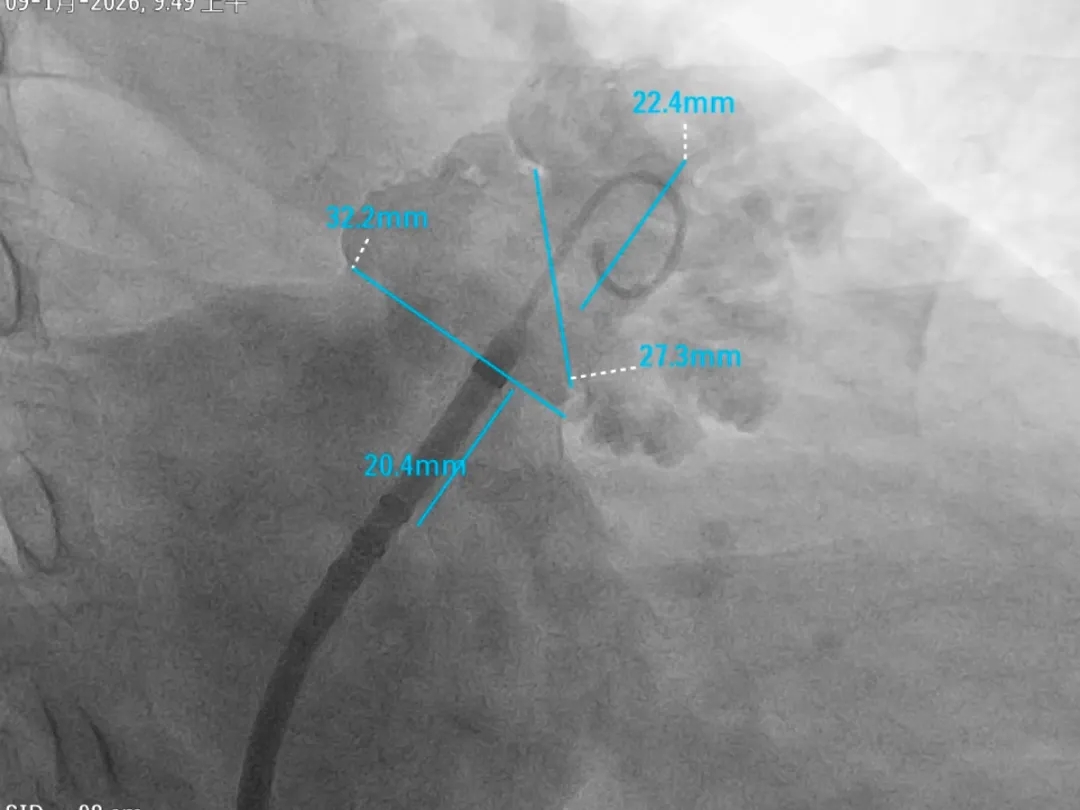

术中DSA肝位造影

心耳呈菜花状,梳状肌发达

心耳内无血栓

开口32.2mm,深度超过22.4mm

封堵策略

穿刺位点及鞘管轴向决定封堵轴向。

输送鞘轴向封堵外口

根据术前超声及术中DSA测量结果,综合判断后选择LAFDQ-32的封堵器进行封堵。

-

心耳的形态判断:结合肝位测量及术前TEE四个角度数据判断该心耳开口椭圆形;

心耳内梳状肌分布判断:DSA造影判断心耳内梳状肌发达;

基于MemoLefort封堵器的设计特点:自适应高回弹镍钛合金骨架可提供径向支撑和贴壁成角倒刺稳定挂靠心耳内部,最终选用LAFDQ-32封堵器,在DSA指导下保持鞘管张力将鞘管维持向上轴向进行封堵。